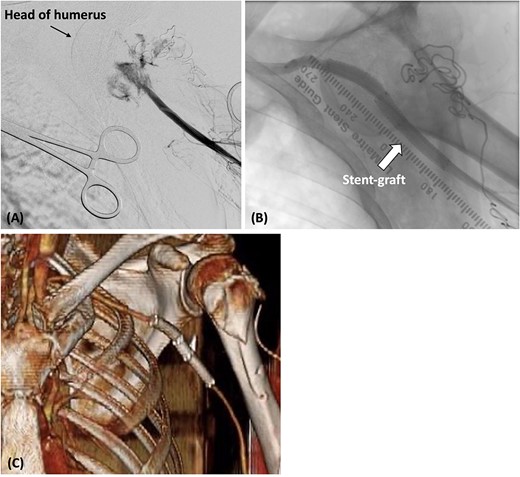

During open reduction, active arterial bleeding was identified from the incision site along with an absent left radial artery pulse. After consultation, we exposed the left brachial artery and inserted a 6-Fr sheath. Angiography revealed a rupture of the axillary artery (Fig. 2A). Because we were unable to penetrate the injured axillary artery with the guidewire from the brachial artery, we placed a 4-Fr catheter (Judkins Right4.0, MEDIKIT CO., Ltd., Tokyo, Japan) at the origin of the left subclavian artery from a right femoral approach. We then advanced a 0.014-inch guidewire (Jupiter FC Guide Wire, Boston Scientific, Marlborough, MA, USA) along a 1.9-Fr/2.5-Fr Fencer microcatheter to the left brachial artery. A 6-Fr snare catheter was inserted through the left brachial artery. The guidewire inserted from the right femoral artery was pulled through the left brachial artery. Intravascular ultrasonography was used to measure the inner diameter of the artery on the proximal and distal sides of the axillary artery injury site (7.7 mm on the proximal side and 6.5 mm on the distal side). Two Gore Viabahn stent grafts (7 × 50 mm and 8 × 50 mm; W. L. Gore and Associates Inc., Flagstaff, AZ, USA) were deployed retrogradely from the brachial artery (Fig. 2B). The stent grafts were expanded using an 8.0 × 60-mm balloon (SHIDEN HP: Kaneka Medical Products, Japan). Final angiography showed good blood flow inside the stent graft with no endoleaks. The reduction of the shoulder dislocation was then completed.

(A) The catheter was inserted from the left brachial artery, and angiography revealed the extravasation of the axillary artery. (B) Stent grafts were placed at the site of the axillary artery rupture to confirm that there was no leakage. (C) Postoperative contrast-enhanced CT revealed that blood flow in the axillary artery was maintained.

Postoperatively, cefazolin was administered intravenously for 1 week after endovascular repair. The radial artery was palpable, and contrast-enhanced CT confirmed that the absence of any leakage from the axillary artery (Fig. 2C). The patient experienced a smooth recovery, except for the presence of brachial plexus palsy. He was discharged on the 10th day, and no infection of the wound or stent grafts was observed during the 5-month outpatient follow-up.